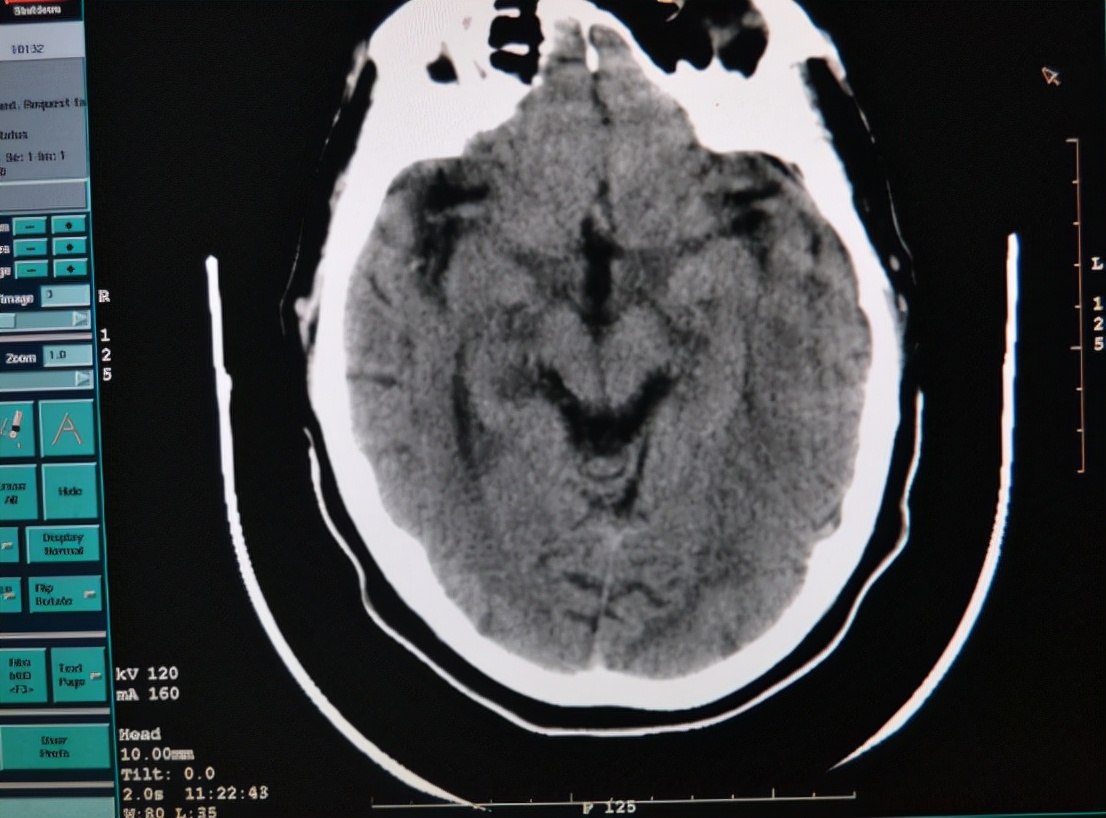

医学上很难从外观上判断出患者是否患有脑出血 ,而是要通过严谨医学手段来检查。因此,患者必须要去医院做脑部CT才能最终确诊。但是平时可以通过一些早期症状来预测是否患有脑出血。

作为早期诊断脑出血的唯一治疗手段,它的准确性非常高。检查颅脑时, 颅内出现高密度影像时,就可以判断此人患上脑出血; 极少数个别情况的患者由于脑出血的面积很小,不易被察觉。